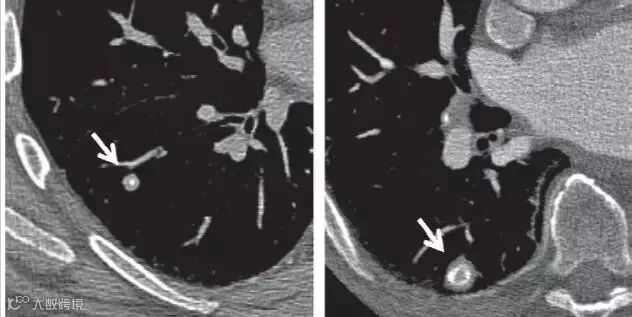

上图为可疑的实性毛刺结节,建议密切随访。